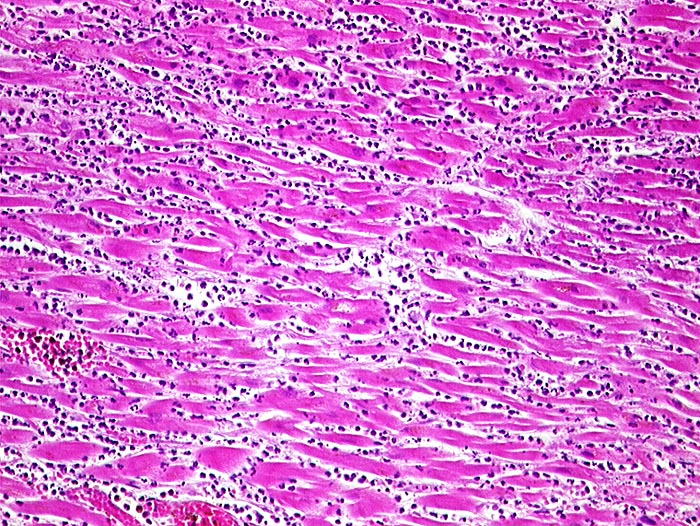

Akuter Myokardinfarkt

vaskulär / Durchblutungsstörung

Herz links

Nekrotische Myokardfasern ohne erkennbare Kerne. Dichtes granulozytäres Infiltrat.

Paninfarkt bei schwer stenosierender Koronarsklerose mit Abgangstenose beider Hauptäste. Alter Verschluss der Arteria coronaria dextra.

Zelluläre Infiltrate sind nach minimal 3 Stunden sichtbar. Kontraktionsbänder entstehen, wenn das hypoxisch geschädigte Myokard sich noch kontrahiert, aber nicht mehr relaxieren kann.